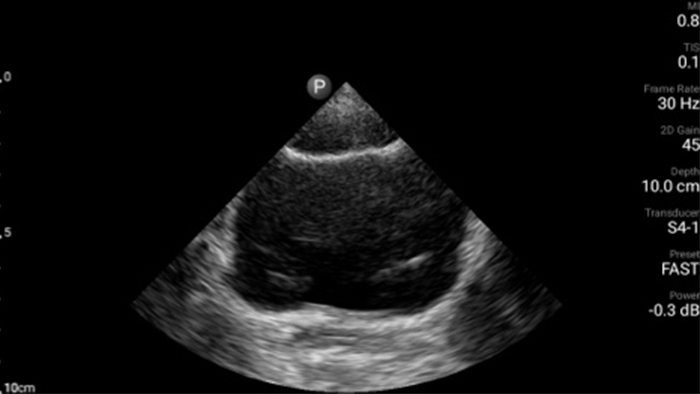

Cada segundo cuenta en la atención cardíaca

Los pacientes que sufren un ataque cardíaco necesitan atención inmediata. Los ajustes cardíacos preestablecidos de Lumify pueden ayudar a los pacientes a ser diagnosticados más rápido para mejorar sus resultados.

• Rango extendido de frecuencias de operación de 4 a 1 MHz • 2D, Doppler a color, Modalidad M, XRES avanzado e imágenes armónicas multivariables • Imágenes de alta resolución para aplicaciones abdominales y cardíacas: las optimizaciones de preajustes de imágenes cardíacas, gineco-obstétricas, pulmonares, abdominales y FAST de Lumify ayudan a la tecnología que salva vidas en entornos prehospitalarios